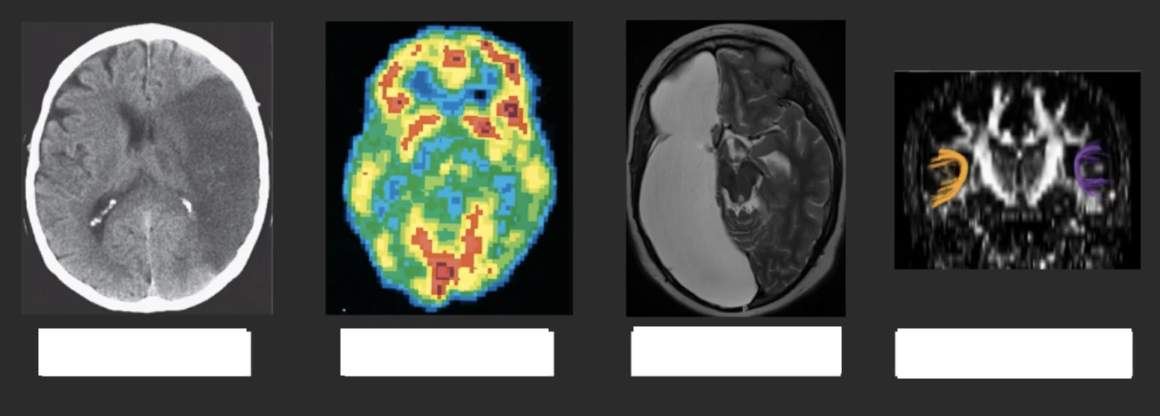

the brain is the source of behavior

cognitive functions localized in specific brain areas